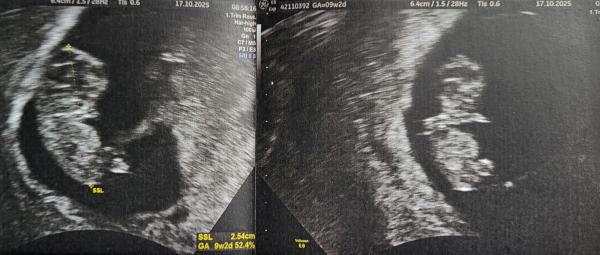

Hallo ihr Lieben.   Wir wollten euch auch nochmal ein Update geben.    Wir sind heute bei 9 plus 2 und es ist alles super zeitgerecht entwickelt. Die Nabelschnur hat auch schon schön pulsiert ☺️  Das Kleine hatte seine Hände am Mund und hat sie bewegt..  total süß, wie so ein kleines Hamsterchen 🐹😍 (sieht man rechts im Bild, ist von oben dargestellt).  Der Ultraschall war heute nochmal Vaginal. Links im Bild sieht man die Nabelschnur auch (rechts hoch zur Plazenta). Was meint ihr könnte es laut Ramzi sein ? 😆 Falls sich wer auskennt 🙈    Wie geht es euch?  Wann ist euer nächster Termin?    Lg und weiterhin alles Gute 🍀🐞